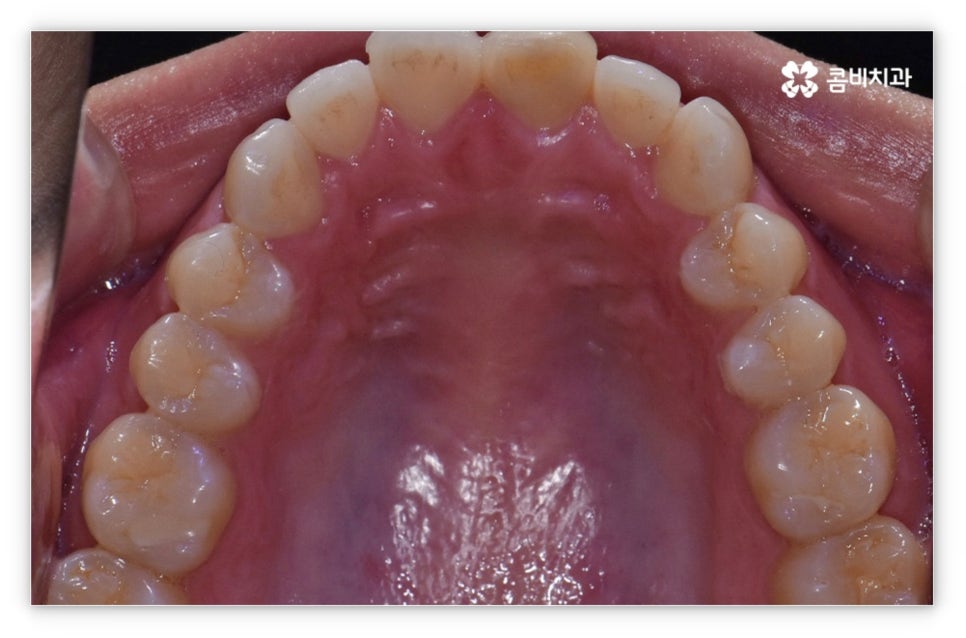

만약 위아래 교합에 별다른 문제가 없고 앞니를 가지런하게 만들 공간이 충분하다고 한다면 부분 교정 치료를 고려해 볼 수 있는데요. 개인차가 있지만 앞니 부분 교정은 보통 36개월 정도 소요되므로 2년 여 정도 걸리는 전체교정에 비해 비교적 짧은 시간 안에 치료가 마무리 될 수 있어요. 환자분들의 상황에 따라 다르지만 보통 비발치 과정으로 진행되며 앞니와 옆 치아 포함 68개 정도의 치아에만 브라켓을 부착하기 때문에 불편함이나 통증 역시 줄어들 수 있습니다.

살펴본 바와 같이 앞니설측교정 의 장점에도 불구하고 아랫니 부분은 장치가 혀에 닿게 되기 때문에 환자분들께서 불편함을 느낄 수 있고 혹시라도 혀가 브라켓에 잘못 쓸리거나 눌렸을 때 통증이 발생할 수도 있으며 발음이 불분명해지는 문제가 생길 수 있는데요. 이러한 이유로 앞니설측교정 에 대해서 고민이 되시는 분들은 윗니 부분은 설측으로, 아랫니 부분은 일반 교정처럼 순측으로 진행하는 콤비 교정에 대해서 알아보시면 좋을 거예요. 위의 사진에서 살펴보실 수 있는 경우가 바로 이렇게 콤비 교정으로 진행한 환자분의 케이스인데 아랫니의 경우 보통 입술에 가려 별로 드러나지 않는 데다가 치아 색상인 세라믹 재질로 된 브라켓을 이용하기 때문에 설측 교정과 비교해도 심미성이 크게 떨어지지 않는다는 것을 알 수 있어요. 콤비 교정의 경우 설측 교정보다 비용적인 부담도 줄일 수 있으니 각 장치에 대한 장단점을 의료진분들과 충분히 상담하셔서 자신에게 맞는 장치를 선택하시면 좋을 거예요.